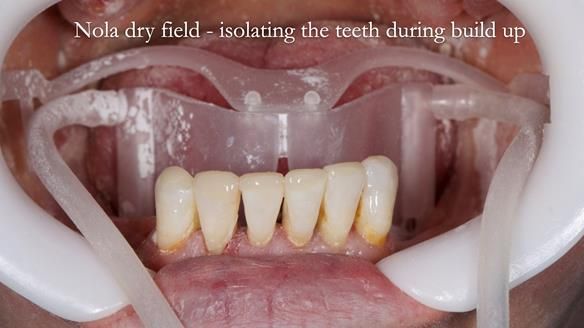

This newsletter describes the full protocol workflow of a complete upper denture and a lower partial denture for Jo.

The clinical situation and treatment process is shown in detail below. I provided the clinical work. Rowan Garstang provided the technical work. This treatment took 25 visits over a period of 12 months.